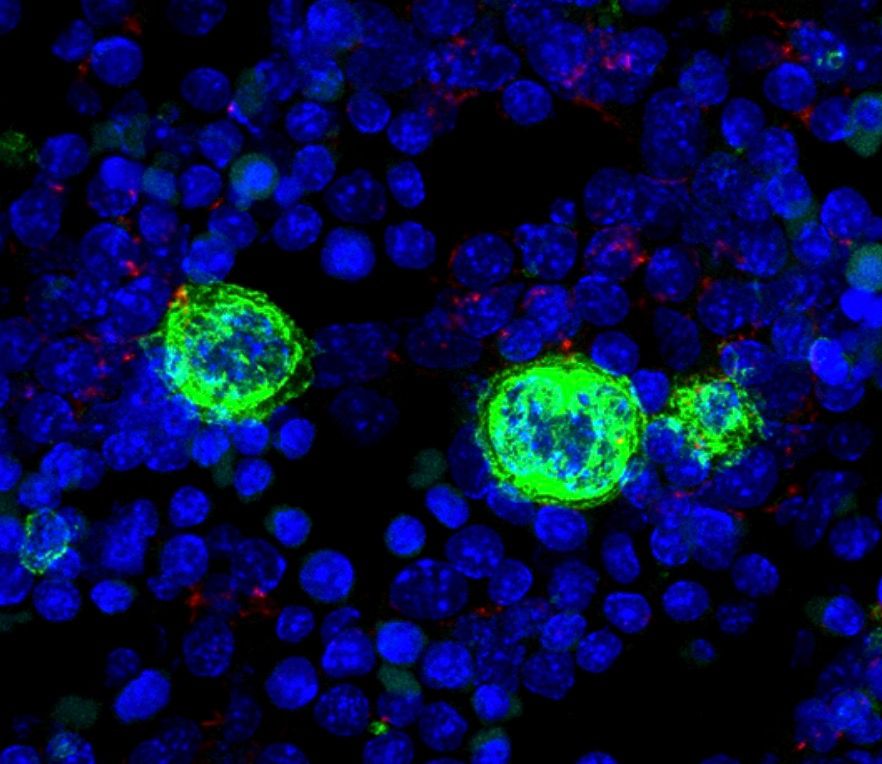

Una de estas células que encontramos en la médula ósea roja es el megacariocito, una célula con unas características muy particulares y de la que seguimos aprendiendo a día de hoy muchas cosas. Además de por su gran tamaño, como ya hemos comentado anteriormente, los megacariocitos se caracterizan por tener un núcleo poliploide (con más de 2 copias de cromosomas). Para conseguir un núcleo de este tipo los megacariocitos sufren un proceso conocido como endomitosis, que consiste en duplicar el material genético sin separar el citoplasma celular (la mayoría de las células después de la mitosis o división del material genético sufren la división del citoplasma o cariocinesis). La endomitosis consigue dar lugar a una célula enorme con un núcleo también de mayor tamaño y contenido genético. Las diferentes etapas que atraviesa el megacariocito, desde la célula hematopoyética madre en la médula ósea (HSC, de sus siglas en inglés hematopoietic stem cell), pasando por diferentes estadios de maduración que podemos diferenciar por su morfología y tamaño, se conoce como megacariopoyesis. En el caso de los humanos este proceso tarda 5-7 días (Imagen 1)

Un hecho relevante en la biología de los megacariocitos es que estas células, junto con los eritrocitos, se generan durante el desarrollo embrionario en la primera onda de diferenciación hematopoyética o hematopoyesis primitiva. Este hecho enfatiza la importancia de estas células y de sus productos: las plaquetas (también llamadas trombocitos) desde el inicio de la vida y en la mayoría de las especies de animales. Estudios realizados en el laboratorio de Inmunobiología del Centro Nacional de Microbiología (ISCIII) han demostrado la importancia de los megacariocitos durante la hematopoyesis en el hígado fetal (órgano que mantiene este proceso en la mitad de la gestación previamente a que la médula ósea adquiera este importante papel). Los megacariocitos embrionarios contactan con las células hepáticas para favorecer su mantenimiento y maduración e interactúan a través del receptor VEGF-A (Hepatology, 2012). Además estos megacariocitos embrionarios tienen algunas características diferenciales con los megacariocitos del individuo adulto como por ejemplo la ausencia de expresión del receptor CD45, una proteína conocida como pan-hematopoyética (Haematologica, 2019). (Imagen 2)